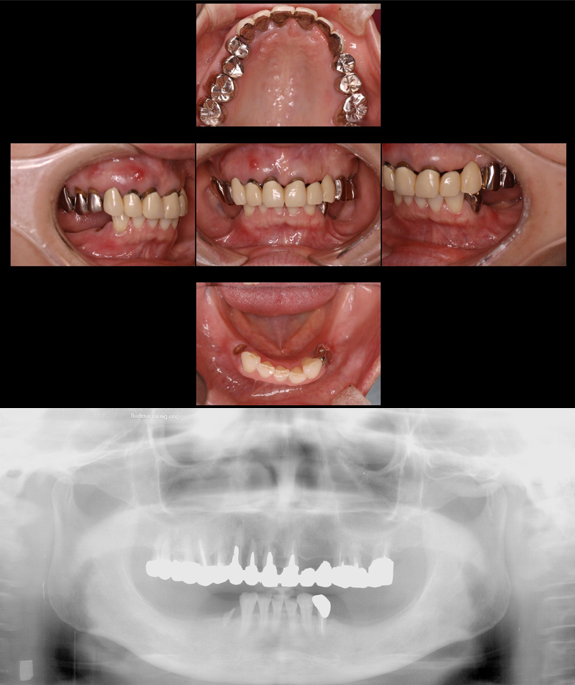

症例3

術前

上下の前歯と奥歯がすれ違っていて最も機能回復が難しいケースです。

術後

インプラントを用いて、しっかりとした噛み合わせを作りしました。